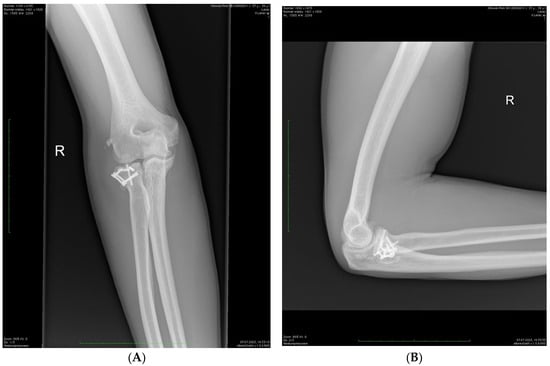

Radiological examinations from the Digital Imaging and Communications in Medicine database were analyzed i.e., X-rays and CT scans after injury (Figure 1), X-rays after surgery and X-rays at the last follow-up visit (Figure 2). Bone union, fracture displacement, periarticular ossification (the Hastings–Graham scale), elbow osteoarthritis, and signs of avascular necrosis of radial head were assessed.

Figure 2. Control X-ray in the same patient 23 months after surgery—AP (A) and lateral (B) projections. Complete bone union and asymptomatic periarticular ossification (Hastings–Graham 1).